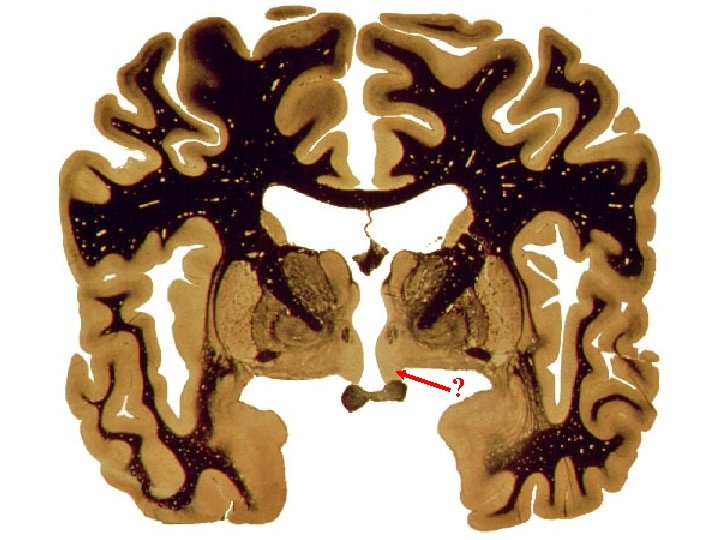

? Olf. system.

Limbic System: Limbic lobe + hippo. , fornix, MMBs, MTT, ant. nuc. thal. , cingulate cortex, cingulum, parahippo. gyrus then into hippo. stria terminalis? Papez circuit? Limbic Lobe